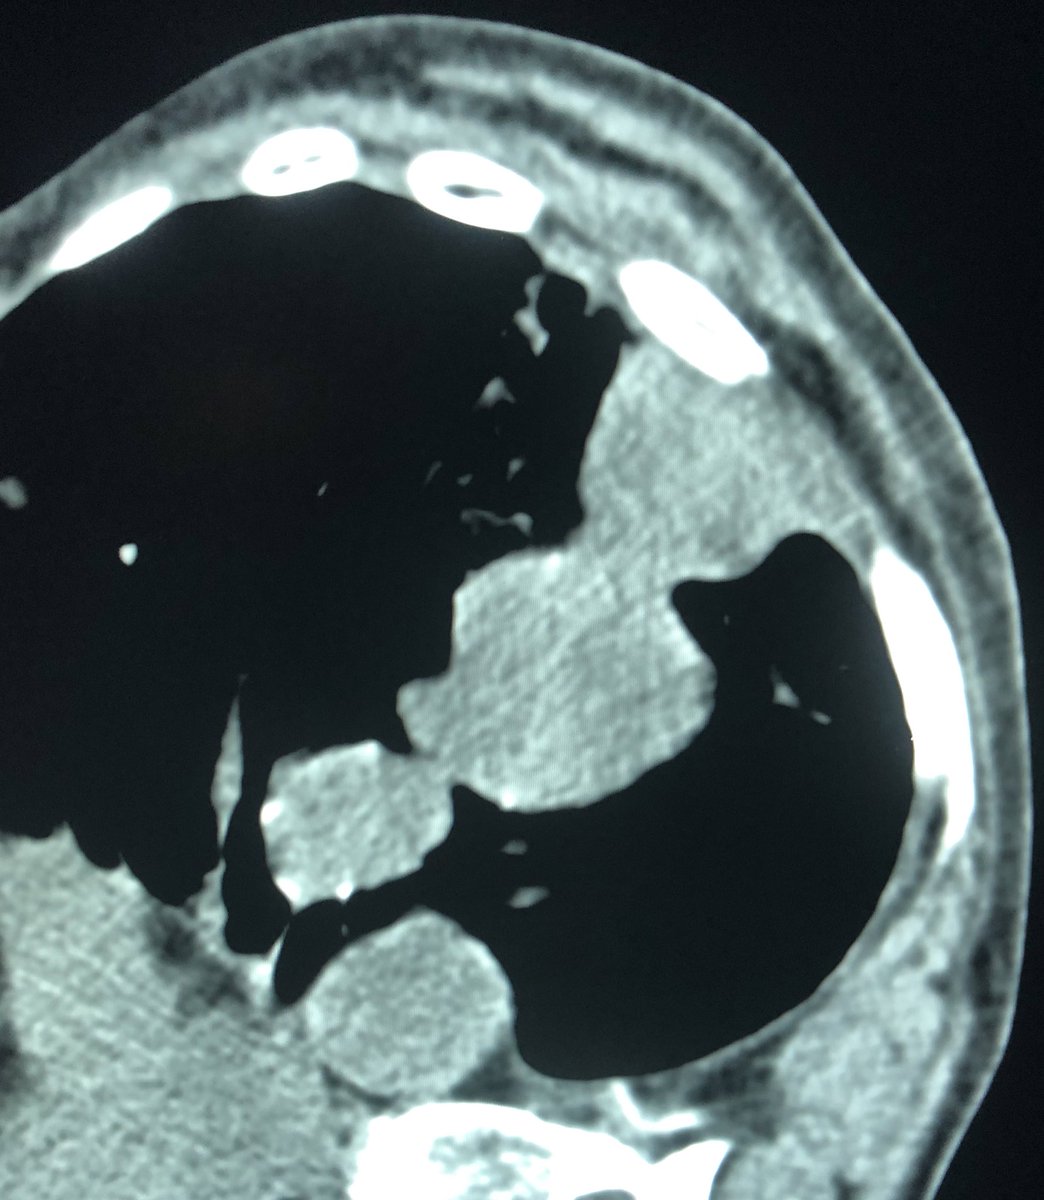

40 yo M severe L flank pain, hypotensive, admit to ICU, CT shows hemorrhage from large renal AML. Angio of torturous AML arteries, subselective run w/active🩸patient stabilized post embo, home several days later #iRad #MedTwitter #FOAMrad #PatientCare @SIR_ECS @SIRRFS @DHidlayVIR